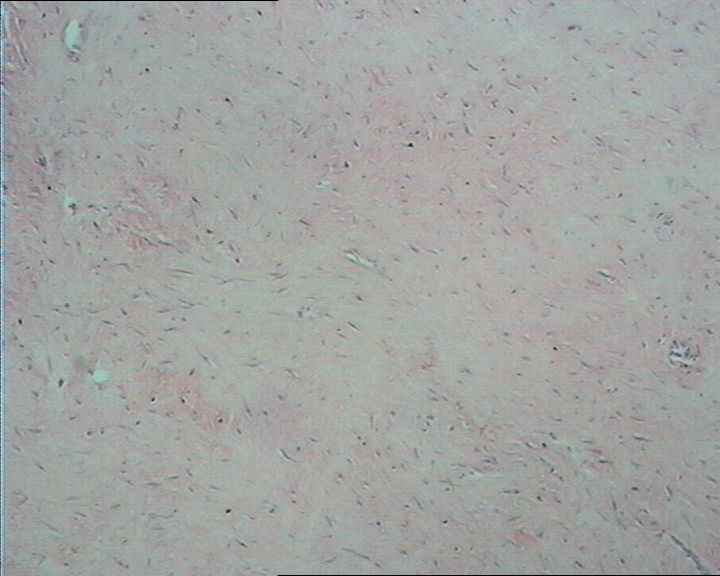

图1

无包膜 3.8cm*3.0cm*2cm 切面灰白淡黄相间

右肘部肿物,无包膜,3.8cm*3.0cm*2cm,切面灰白淡黄相间。